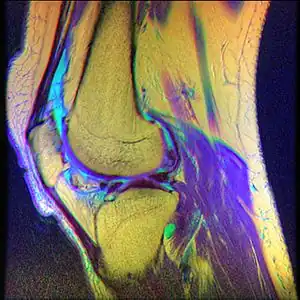

Chondromalacia patellae (also known as CMP) is an inflammation of the underside of the patella and softening of the cartilage.

The cartilage under the kneecap is a natural shock absorber, and overuse, injury, and many other factors can cause increased deterioration and breakdown of the cartilage. The cartilage is no longer smooth and therefore movement and use is very painful.[1] While it often affects young individuals engaged in active sports, it also afflicts older adults who overwork their knees.[2][3]

While the term chondromalacia sometimes refers to abnormal-appearing cartilage anywhere in the body,[15] it most commonly denotes irritation of the underside of the kneecap (or "patella"). The patella's posterior surface is covered with a layer of smooth cartilage, which the base of the femur normally glides smoothly against when the knee is bent. However, in some individuals the kneecap tends to rub against one side of the knee joint, irritating the cartilage and causing knee pain.[16]